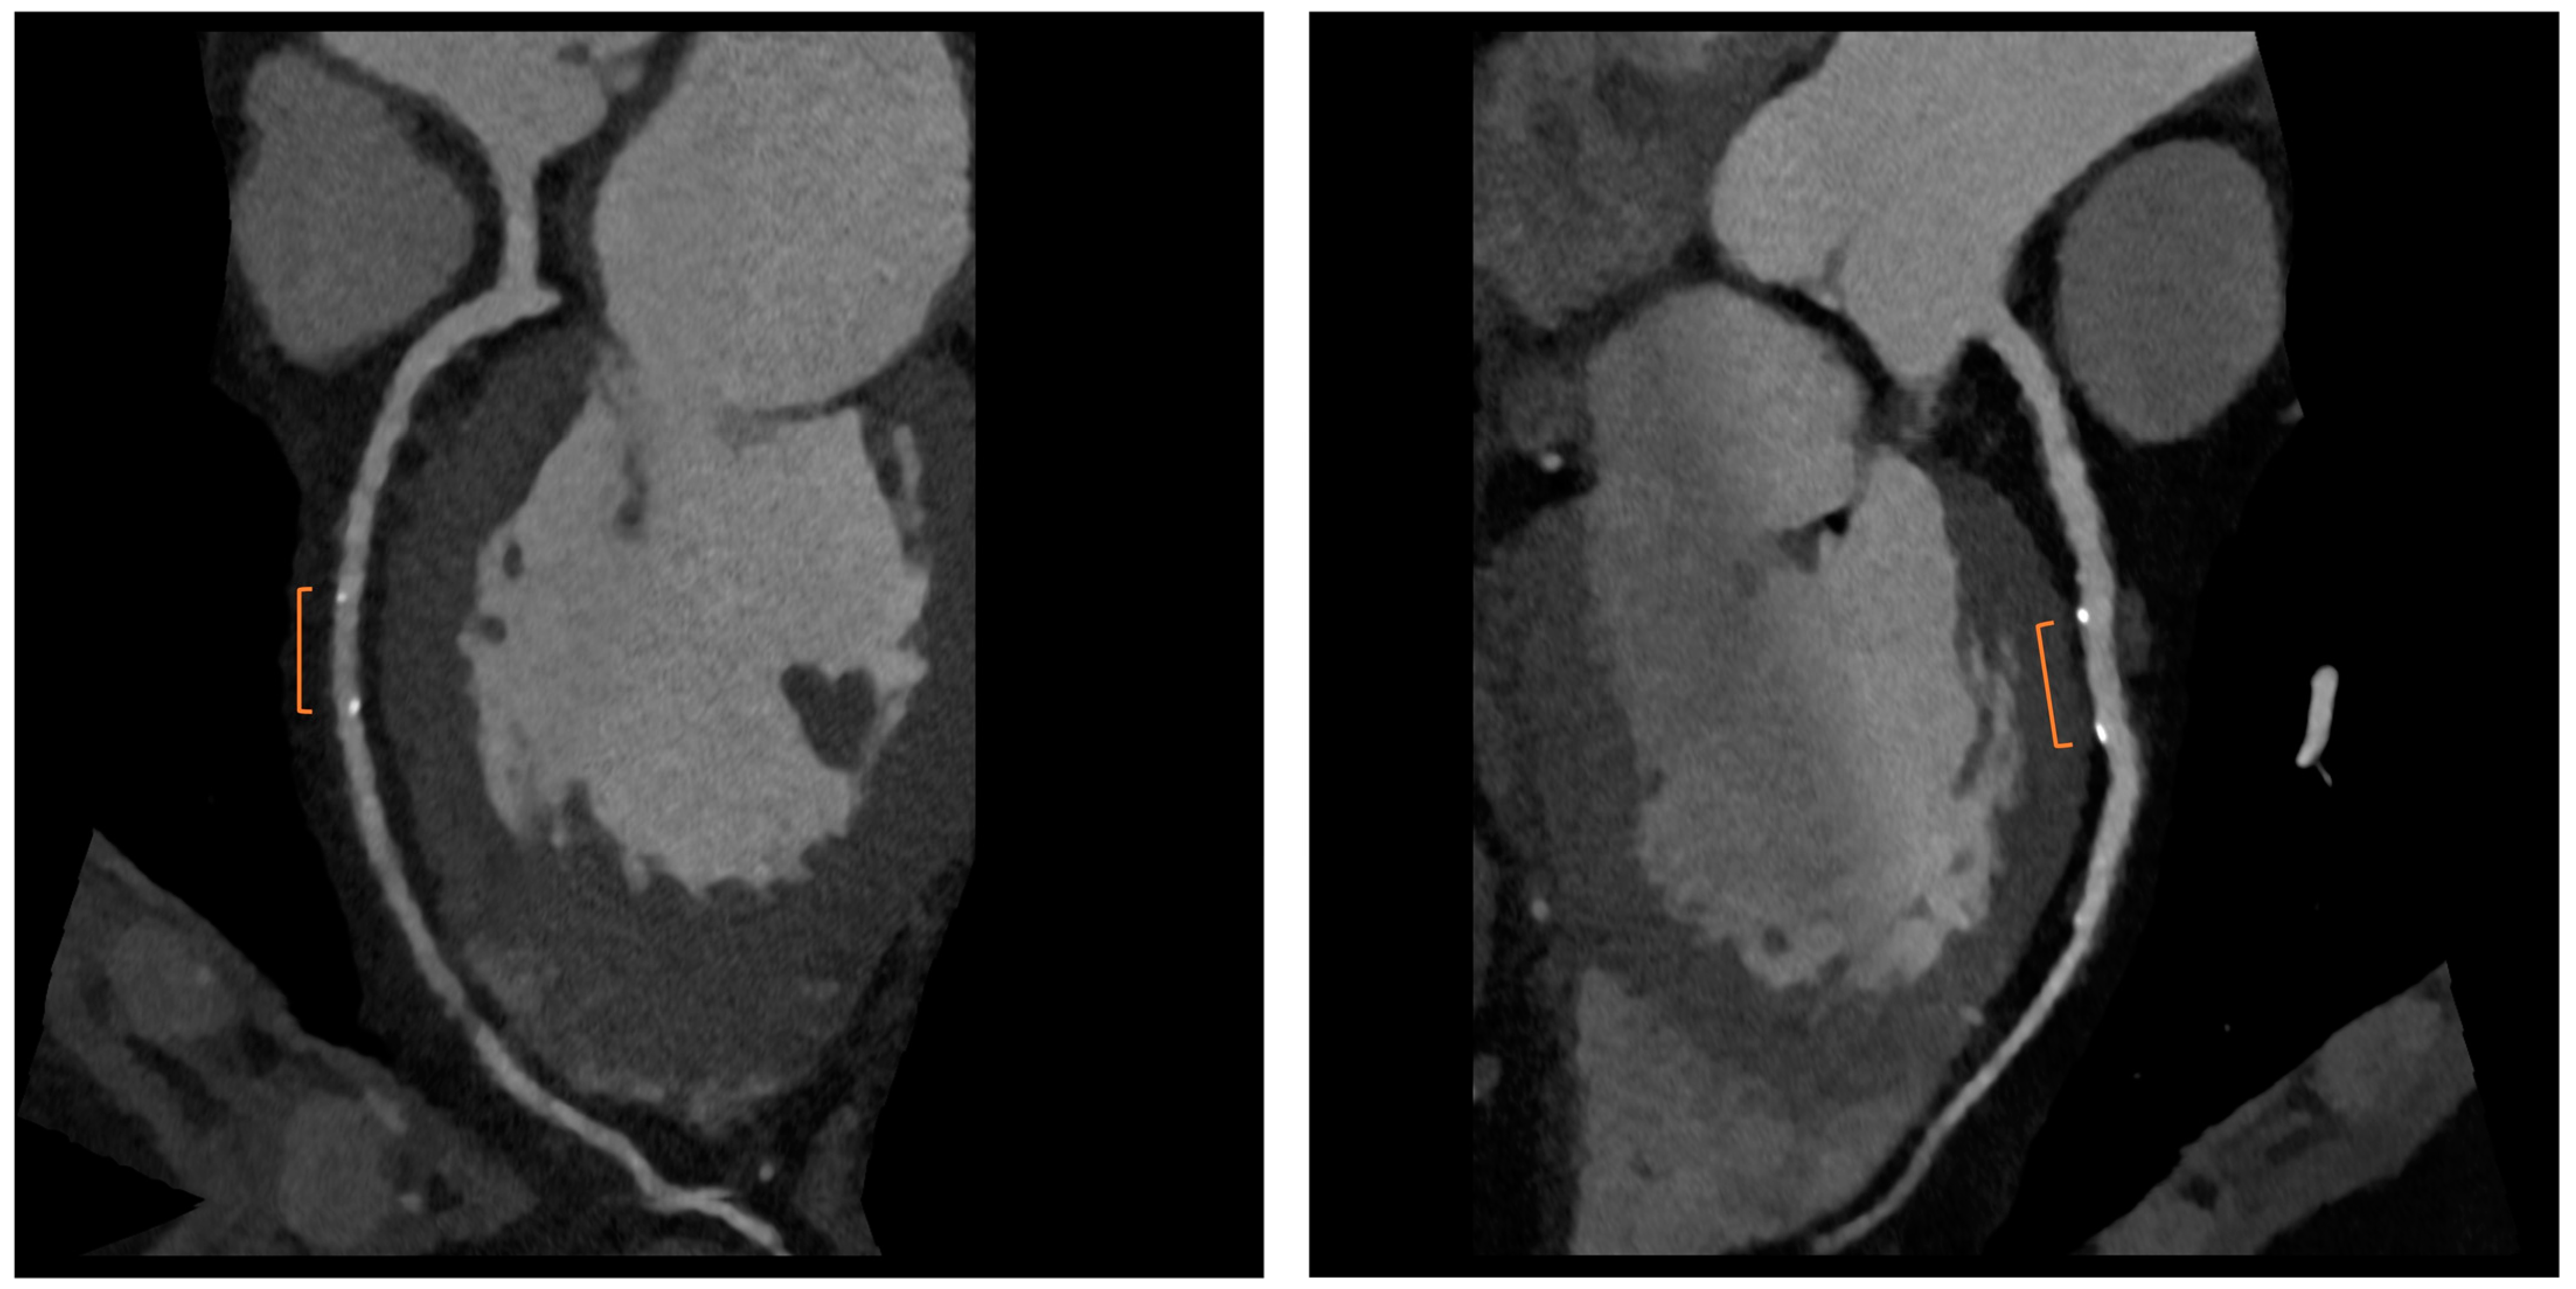

Bioresorbable scaffolds (BRS) were designed to combine the short-term advantages of permanent stents with the long-term benefit of complete reabsorption, facilitating the restoration of vasomotor and endothelial function. This technology helps prevent prolonged inflammation, maintains the integrity of distal bypass grafting sites, and allows unimpeded future vessel imaging. Despite the promising theoretical benefits of BRS, the initial generation of BRS devices exhibited higher rates of stent thrombosis in comparison to other stents [16]. Newer generation devices appear to present a viable alternative to drug-eluting stents in the management of acute coronary syndromes (ACS) for several reasons: their different composition when compared to first-generation BRS, the optimized deployment technique, and the lesion selection. Notably, ACS lesions show specific characteristics based on the pathophysiology of the disease [16]. Thus, various factors create favorable conditions for BRS implantation in ACS patients, including the vulnerable nature of the plaque, minimal calcification, the presence of a thrombus, and the relative youth of patients. BRS is radiolucent except for two metallic radio-opaque markers located at both extremities. This design feature aids in visualization during imaging procedures, ensuring accurate placement and monitoring of the scaffold. Thus, CCTA can delineate the contours of the scaffolded segment: markers easily enable the location of where BRS was implanted, and they can be distinguished from calcification because of the difference in attenuation [17]. Figure 3 shows a CCTA analysis of scaffolded coronary segments: as highlighted by orange brackets, there is evidence of two little markers of the scaffold that appear completely reabsorbed: indeed, no struts are detectable, and the vessel lumen can be analyzed in depth also in the scaffolded part with no evidence of plaque proliferation. The diagnostic accuracy of coronary CT angiography in poli-LLA (poly-L-lactide) Everolimus scaffold was studied in the ABSORB II study (A Bioresorbable Everolimus-Eluting Scaffold Versus a Metallic Everolimus-Eluting Stent II) [6]. The study provided the randomization of enrolled patients to receive treatment with BRS or drug-eluting stent. At the 3-year follow-up, patients treated with BRS underwent coronary angiography with intravascular ultrasound (IVUS) evaluation and CCTA. The study demonstrated that the CCTA diagnostic accuracy for detecting in-scaffold obstruction and luminal dimensions was similar to invasive coronary angiography (ICA) and IVUS. Analyzing scaffold segments, the sensitivity, specificity, and negative predictive values were 71%, 82%, and 97%, respectively, using IVUS as a reference. One limitation of this study was its use of a 3-year follow-up period, which did not address the crucial question of assessing the occurrence of restenosis within the initial 12 months. It is during this period that most restenosis events occur, coinciding with the presence of BRS with thicker struts in place [18]. Salinas P et al. performed the first case series of Magnesium bioresorbable scaffold investigated with CCTA at 1 year of follow-up [7]. The CCTA in-scaffold percentage diameter stenosis and area stenosis were 22% and 39%, respectively, underlying plaque growth. Additionally, performing plaque characterization, the segments treated with RMS showed that the most common component of the plaque was the fibrous one (69% of the cases), suggesting that RMS allows for the stabilization of culprit lesions [7]. Furthermore, anatomical findings can be combined with noninvasive fractional flow reserve derived from CCTA (FFR-CT) to distinguish the presence or absence of flow-limiting disease [19]. A study by Tonet E et al. investigated the performance of CCTA and FFR-CT in 26 patients treated with Magnesium bioresorbable scaffold: all patients underwent CCTA 18 months after BRS implantation. The left anterior descending artery was the most commonly affected vessel. CCTA revealed patent scaffolded segments, with complete strut reabsorption observed in 93% of cases. FFR-CT demonstrated to be feasible in scaffolded segments with a median value of 0.88 [0.81–0.91]. Figure 4 shows a case from the above-reported study: BRS (orange bracket) appears to be characterized by plaque proliferation with a prevalent calcific component. FFR-CT analysis highlighted a significant stenosis related to the plaque. In conclusion, these results suggest that CCTA plus FFR-CT is a valuable noninvasive tool for the assessment of coronary arteries in subjects treated with BRS. Scaffolded segments can be easily distinguished, allowing for quantitative measurements and the calculation of noninvasive FFR. The analysis also indicates a tendency to observe plaque stabilization in the scaffolded segments with fibrosis and calcium [8]. However, further evidence is needed in this setting of BRS patients.

Figure 3.

CCTA assessment of BRS. Orange brackets highlight the two markers of BRSs whose struts result in complete reabsorption. The vessel is also well analyzed in the scaffolded segment.

Figure 4.

Anatomical and functional assessment of ISR in a scaffold (orange bracket). ISR appears to be characterized by a major calcific part, and the stenosis results were significant under the FFR-CT assessment. FFR-CT was performed with DeepVessel FFR (DVFFR) software (Keya Medical, Seattle, WA, USA).